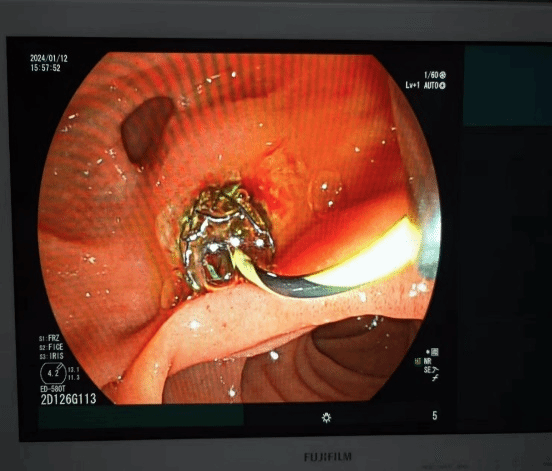

ERCP